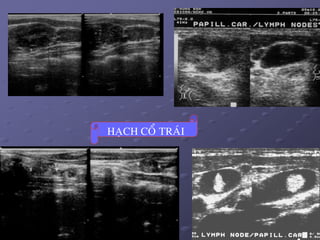

 Ñaëc ñieåm haïch di caên: maát hình baàu duïc, thöôøng hình

troøn, khoâng coøn roán haïch echo daày ôû vuøng trung taâm duø

haïch kích thöôùc nhoû. Ñoâi khi haïch coù caáu truùc echo daày

hôn cô, ñoàng nhaát, hay hoaïi töû, coù theå coù vi voâi hoùa trong

haïch. Ñoâi khi haïch mang hình aûnh gioáng nhö nhaân ung

thö nguyeân phaùt cuûa TG.

HAÏCH COÅ TRAÙI